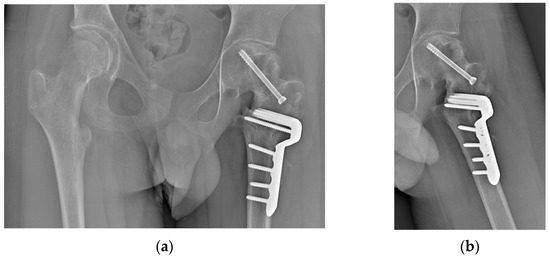

2.2. Surgical Procedure

2.4. Results